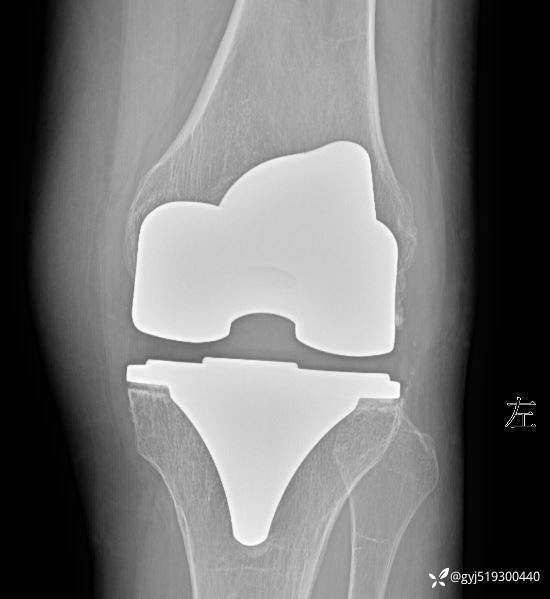

患者女性,68岁,两年多前行左侧膝关节置换,术后断断续续疼痛,期间膝关节肿痛明显,外院抽液化验后考虑滑膜炎。既往无高血压,糖尿病,类风湿等

本次入院后,见膝关节肿胀明显,皮温稍高,外侧间隙压痛,活动度因肿胀轻度受限,检查炎性指标均正常。予以膝关节穿刺抽液,抽出50ML血性液。